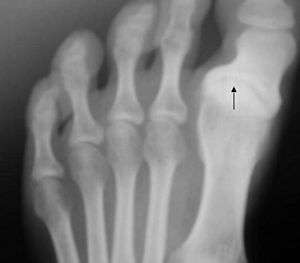

| Radiography of the left foot of a young male showing progressive Hallux varus | |

Hallux varus is a deformity of the great toe joint where the hallux is deviated medially (towards the midline of the body) away from the first metatarsal bone. The hallux usually moves in the transverse plane. Unlike hallux valgus, hallux varus is uncommon in the West but it is common in cultures where the population remains unshod.